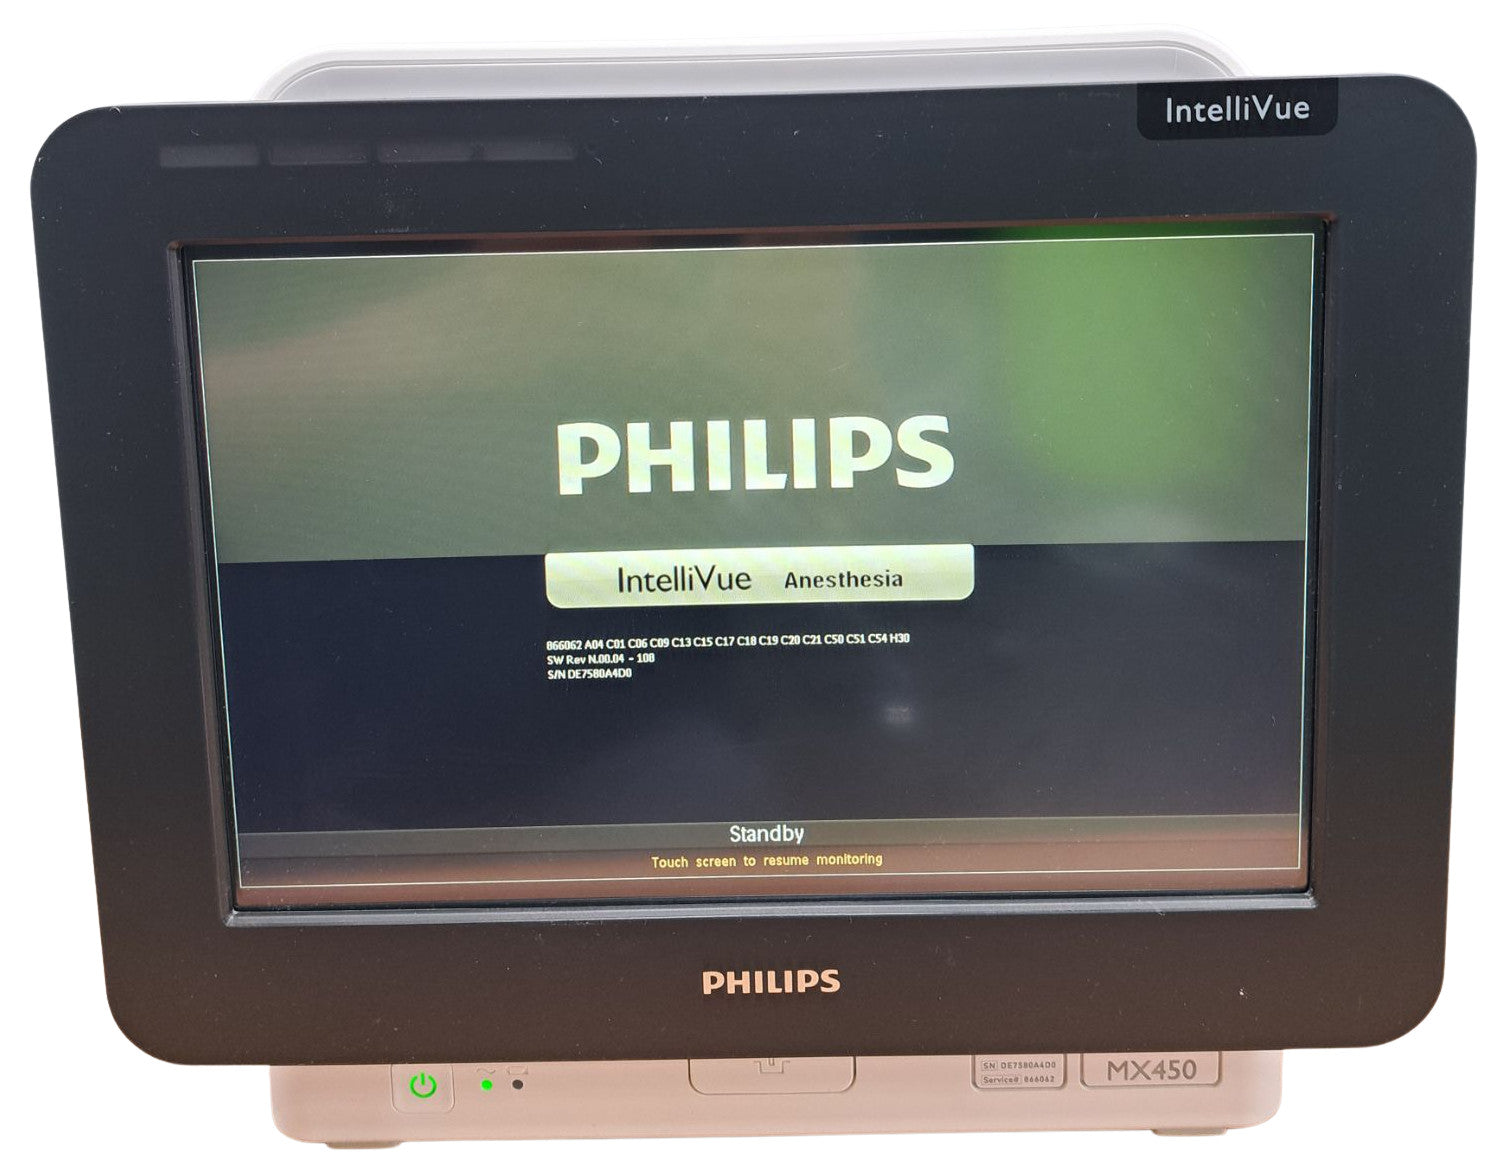

PHILIPS INTELLIVUE MX450 BEDSIDE PATIENT MONITOR

Sale price$ 1,500.00

PHILIPS INTELLIVUE MX450 BEDSIDE PATIENT MONITOR

Sale price$ 1,500.00